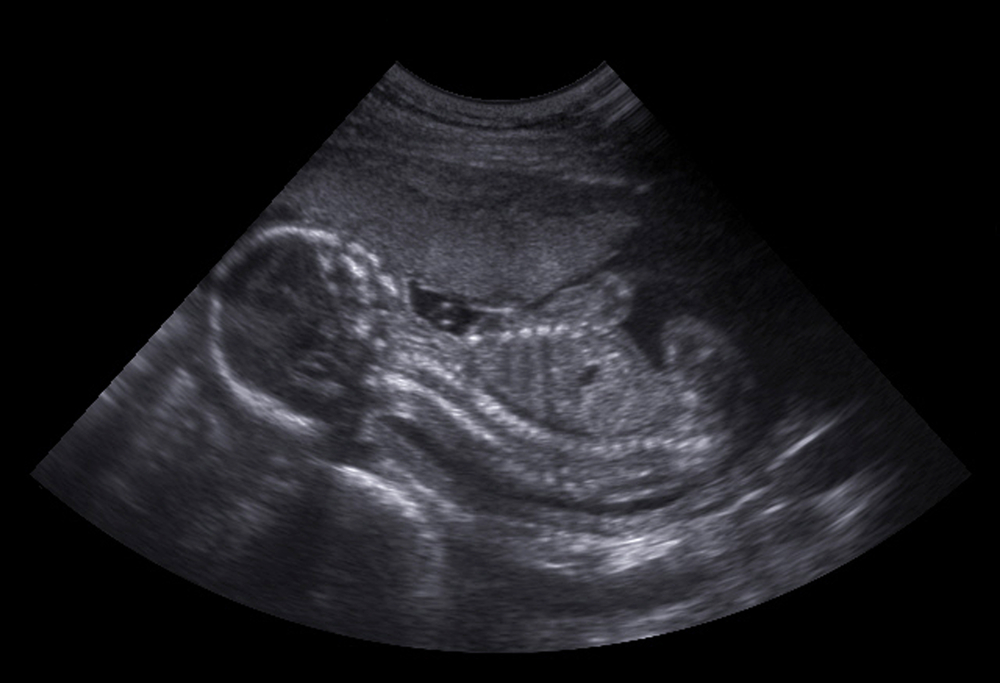

Quanto aos sintomas, a gestante não percebe nenhuma diferença na gravidez. Somente com exames de imagens e no nascimento que o gêmeo parasita se torna perceptível. Em contrapartida, há indivíduos que não aparentam nenhuma anormalidade.

Logo, só descobrem que possuem um gêmeo parasita ao realizar um ultrassom abdominal que detecta uma massa na região, segundo a especialista da BP.

A principal forma de identificar o fetus in fetu é por meio dos exames de imagem. Ou durante o pré-natal, se a malformação for evidente, ou em algum momento da vida desse bebê.